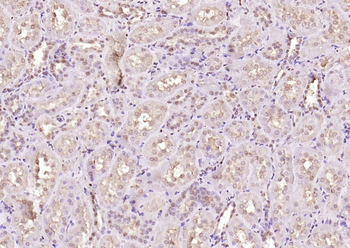

ICC, IF, IHC-Fr, IHC-P, WB

Human, Mouse, Rat

Zebrafish

Rabbit

Recombinant

Unconjugated

50 μl, 100 μl, 25 μl - Anti-KIFC1 Antibody [orb865535]